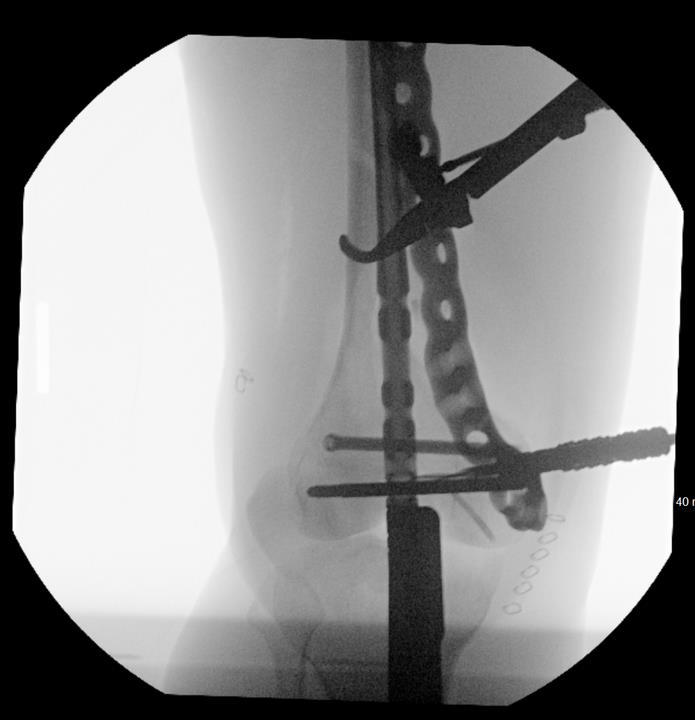

Summary Designed with SOMA (Stryker Orthopedics Modeling and Analytics) which includes a database with CT scans from hospitals across the world and state of the art algorithms that analyze shape variability, bone density, and implant fit Designed to link with the T2 Alpha Femur Retrograde Nail when using nail plate combination fixation Eight distal T20 screw holes, including 1 linking hole and 1 AP hole designed to capture Hoffa fragments Related Implants The Pangea® Femur Reconstruction System includes Lateral NPC Plate Medial NPC Plate (this topic) T2 Alpha™ Femur Retrograde Nailing System Design Tapered end allows for atraumatic submuscular insertion Staggered screw holes designed to enable surgeon to choose points of fixation and allows for placement of screws around an intramedullary implant or a prothesis AP hole screw hole trajectory that is designed to capture a "Hoffa Fragment" (Posterior Medial Condyle) Variable-angle screw holes circular universal holes accept non-locking screws, and locking screws within a 30° cone Proximal twist metadiaphyseal twist allows for screw placement anterior to posterior Linking hole designed to allow for seamless linking of the plate to a T2 Alpha Femur Retrograde Nail using an AlphaLink Dowel Indications Indications partial articular medial tibial plateau fractures medial plateau fragments in bicondylar tibial plateau fractures metaphyseal fractures epiphyseal fractures extra-articular proximal tibial fractures Contraindications active or suspected infection at the surgical site severe local inflammation around the operative area hypersensitivity or allergy to implant materials inadequate soft-tissue coverage over the implant Anatomy Osteology medial tibial plateau medial femoral condyle intercondylar eminence attachment point for cruciate ligaments tibial tuberosity insertion of the patellar tendon Muscles anteromedial tibia sartorius gracilis semitendinosus popliteus stabilizes and unlocks the knee Ligaments medial collateral ligament anterior cruciate ligament posterior cruciate ligament medial meniscus Approach Surgeons may use a standard medial, medial parapatellar, or medial subvastus approach to the distal medial femur Technical specifications Plate material type II anodized titanium (Ti6Al4V) Two plate lengths 155mm and 265mm Plate thickness 5mm Left and right anatomic options Screws Multiaxial locking 5.0 (14-120 mm) 4.0 (14-95mm) 5.0 (10-20mm) Cortex 4.5 (14-150mm) Cancellous 6.0 (20-150mm) 6.0 (30-150mm) 6.0 (45-150mm) Cable plug washer AlphaLink Dowel 50-90mm